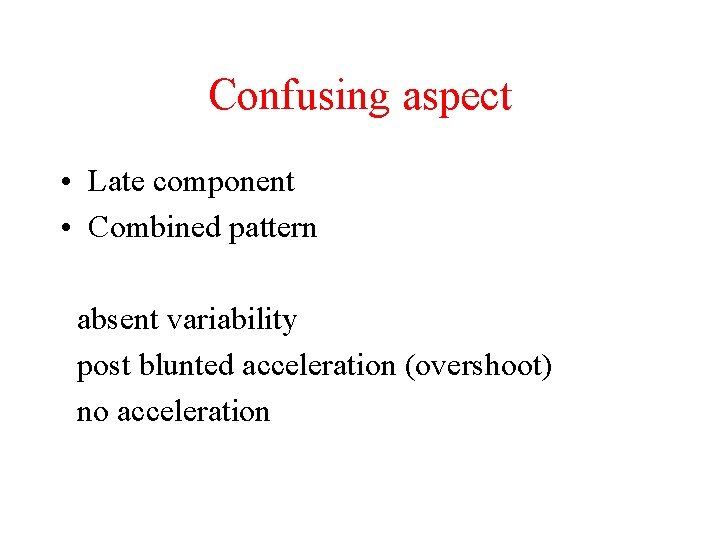

Confusing aspect • Late component • Combined pattern absent variability post blunted acceleration (overshoot) no acceleration